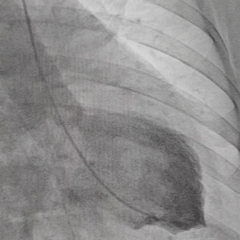

Imagem da semana

Ventriculografia evidenciando dissincronia interventricular, associada a fibrilação atrial e queda da fração de ejeção do VE. Bonito, não é?!